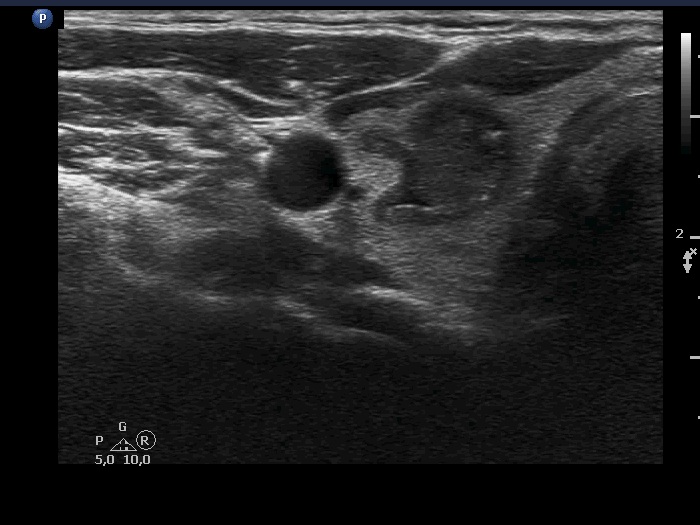

Ultrasonography. The thyroid was echonormal and had multiple moderately hypoechoic and hyperechoic nodules which showed various degrees of cystic degeneration. The largest nodule in the right lobe was dominantly cystic and presented with minimally hypoechoic solid part which included hyperechoic figures. The largest nodule in the left lobe had irregular margins.

The right nodule presented with a patchy echonormal area having punctate echogenic foci, a pattern resembling amyloid deposit.

The left nodule had irregular borders.